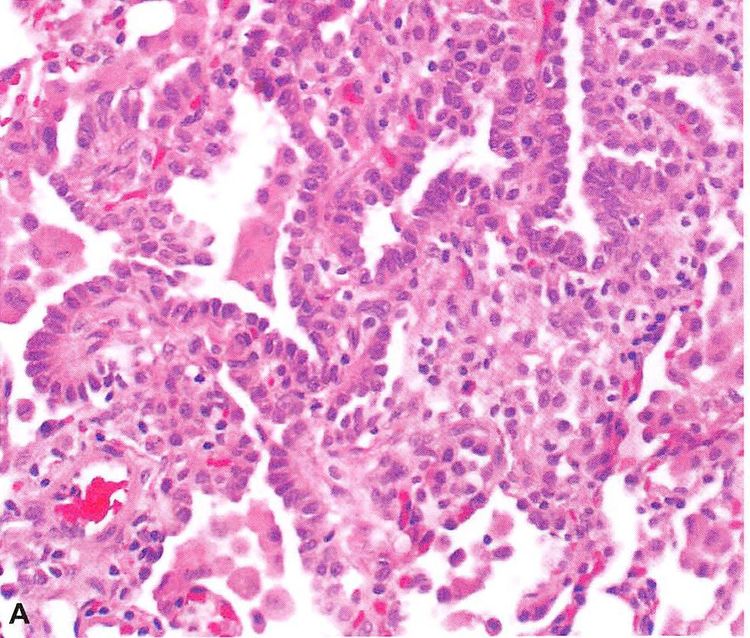

主要研究者之一阿尔伯特·爱因斯坦医学院的基因学教授西蒙·斯皮瓦克(Simon Spivack)说:“这些肺部(上皮)细胞可以存活好几年,甚至几十年,因此随着年龄的增长和吸烟量的增加,所累积的变异越来越多。在所有类型的肺部细胞中,这些细胞最容易出现癌变。”

检查结果显示,即使是非烟民,随着年龄的增长,其肺部细胞累积的变异也在逐渐增多。当然,烟民肺部细胞累积的变异明显更多。“这证明,吸烟的确增加细胞变异的几率,也在增加患癌的几率,这与以前提出的理论一致。这就是为什么非烟民中患肺癌的比例很低,但是10%~20%的烟民都罹患肺癌。”

不过,这项研究发现了一个新的线索:在烟民组中,细胞的变异随着烟量的增加而直线上升,患癌的可能性也在增加,然而,烟量超过23包·年后,细胞变异的数量不再增加。